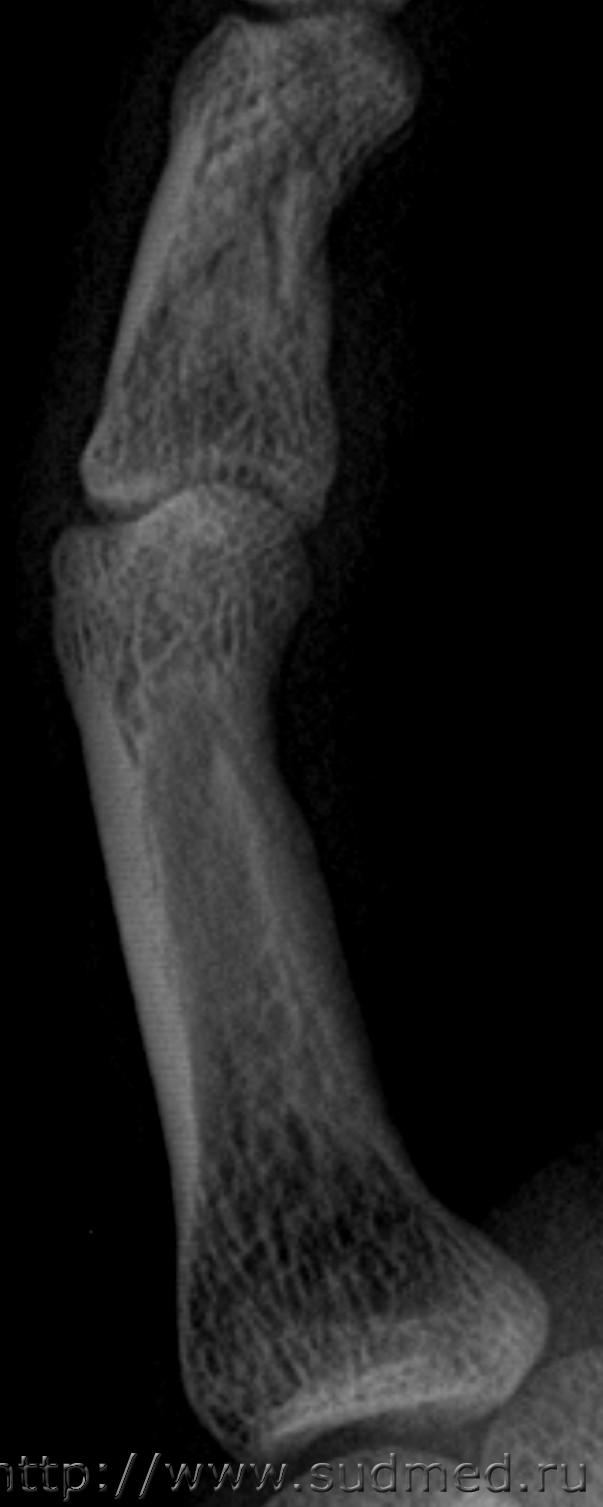

Второй снимок, 100 дней после травмы. На рентгеновской пленке.

Заключение: на представленной рентгенограмме 5 пальца левой кисти в 2-х проекциях от (100 после травмы) костно-травматических изменений не выявлено.

Снимок через 100 дней после травмы на рентгеновской пленке остался у экспертов, я его отсканировал перед тем как отдать:

Больше вопросов и предположений вызывает не основная, а средняя фаланга. Если бы она так выглядела через 100 дней после травмы, можно было бы согласиться, что несколько месяцев назад был перелом средней фаланги. Через 13 дней перелом так выглядеть не может. Вероятно, имеется какая-то индивидуальная особенность или когда-то давно (многие месяцы-годы назад) был перелом средней фаланги мизинца. Основная фаланга особых вопросов не вызывает: согласен с рентгенологами по поводу отсутствия достоверных рентгенологических признаков перелома.